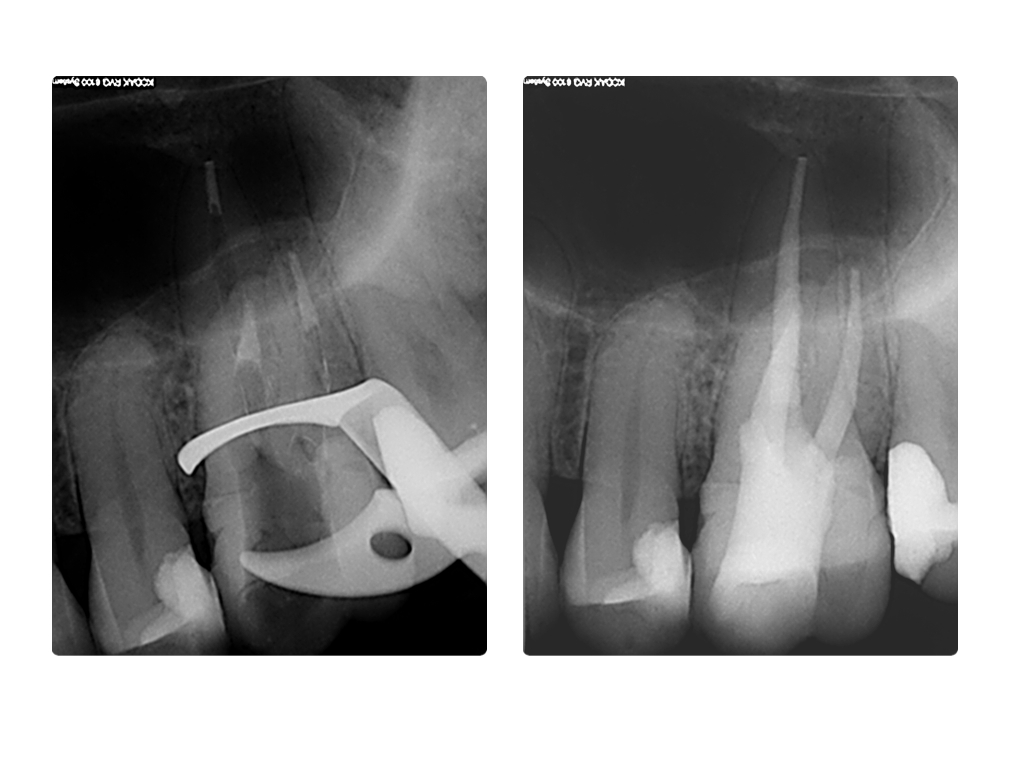

WS8.011

1024 × 768

Instrumentenfraktur (3b)